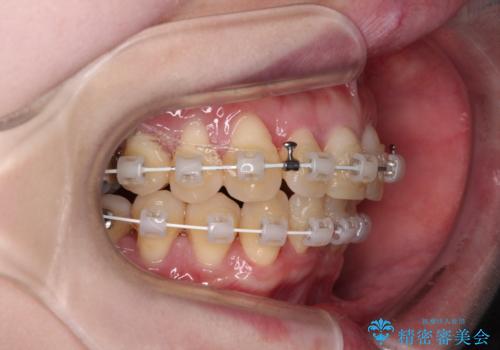

八重歯と先天欠損の歯列 ワイヤー矯正ですっきりと

- 八重歯と正中のズレを気にして来院された患者様です。

上顎左側が八重歯になっており、上顎正中が左側にずれていました。

上顎左側の第一小臼歯を抜歯し、補助装置を用いて正中位置を改善しながら八重歯を解消していくこととしました。

下顎前歯が1本欠損していたため、上下正中の位置が合わせるという目標はなく、鼻筋に上顎正中を合わせていくように移動を行いました。